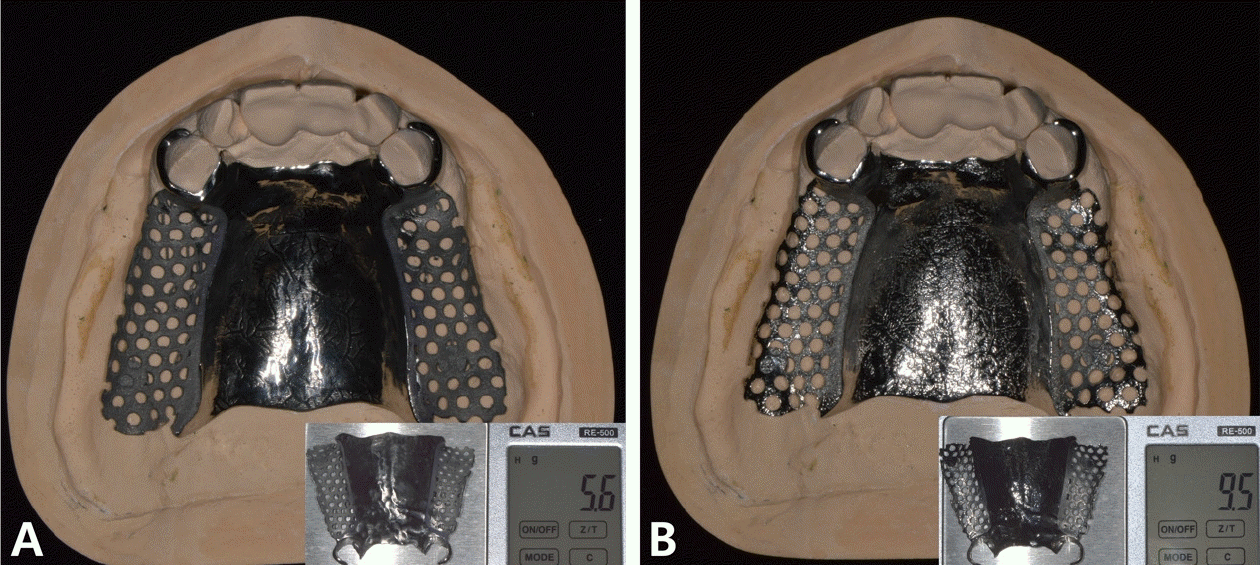

본 증례의 환자는 76세의 여성으로 상악 6전치만 잔존한 상태로 상악 가철성 국소의치의 제작을 위해 내원하였다. 상악은 6전치 중 상악 우측 견치와 좌측 견치의 상태는 동요도 및 파절 상태 없이 양호하였고, 상악 우측 측절치는 총생 상태였으며, 상악 우측 중절치와 상악 좌측 측절치를 이용해 3본 고정성 가공의치 형태로 상악 좌측 중절치의 수복이 되어 있는 상태였고, 상악 잔존 치조제의 상태는 중등도의 흡수 상태가 관찰되었다. 하악은 하악 좌측 제 2소구치는 잔존 치근 상태였다(Fig. 1). 상악의 경우엔 임시의치를 사용중이었고, 잔존 치근 상태인 하악 좌측 제 2소구치는 발거를 진행하였다. 전신병력으로는 B형 간염, 신장 투석, 파킨슨, 당뇨, 고혈압 및 협심증으로 다양한 약을 복용중이었고 비용 및 전신병력의 이유로 임플란트와 같은 수술적인 치료방법의 치료는 어려운 상태였다.상악은 양측 구치부의 결손이 있는 Kennedy Class I 으로 분류하고, 후방 결손부의 수복을 위해서 상악 가철성 국소의치의 제작을 진행하기로 결정하였다. 상악 가철성 국소의치의 디자인은 양측 상악 견치에 후방연장 국소의치의 유지를 위해 설면 레스트와 원심 유도면, 조직 언더컷으로 인해 RPA 클라스프를 설계하였고, 잔존 치아의 개수가 적어 주연결장치는 구개부를 대부분 피개하는 구개판형 연결장치를 설계하였다. 간접 유지의 역할을 위해 추가적인 설면 레스트의 부여를 고려하였으나 양측 측절치에 설면 레스트의 형성은 상악 우측 측절치의 총생 및 상악 좌측 측절치의 기존 보철 수복물로 인해 한계가 있었다(Fig. 2). 의치의 무게로 인한 탈락을 최대한 보완해보고자 금속 구조물의 제작을 코발트-크롬 합금보다는 보다 가벼운 특징을 가진 티타늄 합금(Ti-6Al-4V)을 이용하여 제작하기로 결정하였고, 7년 이내 요양급여를 통한 보험의치 적용을 받은 기록이 있어 비보험 진료로 진행하기로 하였다.해당 수복의 진행을 위해 양측 견치에 설면 레스트 시트를 구강 내 직접 형성 하였고 삽입 철거로를 고려하여 원심면의 치질 성형을 시행하였다(Fig. 2). 이후 개인 트레이를 제작 후 부가중합형 실리콘(Selection-K V.P.S, Shinhung Co., Seoul, Korea)를 이용해 기능인상채득을 시행하였다(Fig. 3). 이후 주모형을 제작하였고 제작된 주모형을 모델 스캐너(DOF Freedom HD, DOF Inc., Seoul, Korea)를 이용해 스캔하여 디지털 데이터를 형성하였다(Fig. 4). 이후 디지털 데이터를 이용하여 CAD 프로그램(3Shape dental system, 3Shape Inc., Copenhagen, Denmark)를 이용하여 금속 구조물을 디자인하였다(Fig. 5). 이후 해당 디자인된 금속 구조물을 선택적 레이저 용융 방식(SLM)의 3D 프린터(David 1.0, Merain Co., Incheon, Korea)를 이용하여 티타늄 합금(Ti-6Al-4V)으로 금속 구조물을 제작하였다. 또한 티타늄 합금과의 무게 비교를 코발트-크롬 재질의 금속 구조물도 티타늄 합금(Ti-6Al-4V)의 금속 구조물 제작에 사용한 동일한 CAD 파일을 이용하여 3D 프린팅을 통해 제작하였다.제작한 티타늄 합금(Ti-6Al-4V)과 코발트-크롬 합금의 금속 구조물의 후처리를 완료 후 주모형에 적합도 확인 및 무게 측정을 시행하였으며, 티타늄 합금(Ti-6Al-4V) 금속 구조물의 무게는 5.6g 이었고, 코발트-크롬 합금의 무게는 9.5g으로 티타늄 합금(Ti-6Al-4V)의 무게가 코발트-크롬 합금보다 41% 정도 더 가벼운 무게를 나타냈다(Fig. 6).제작된 티타늄 합금(Ti-6Al-4V) 금속 구조물의 적합을 환자 구강내에서 확인하였고, 이후 기록상을 제작하여 악간관계 기록을 채득 후 교합기에 부착하여 치아배열을 시행하였으며, 균일하게 중심교합 시 균일한 교합접촉을 이루는지 확인하였다(Fig. 7).

Figure 6.

The titanium alloy (Ti-6Al-4V) framework (A) weight 5.6 grams, while the Co-Cr alloy framework (B) weights 9.5 grams